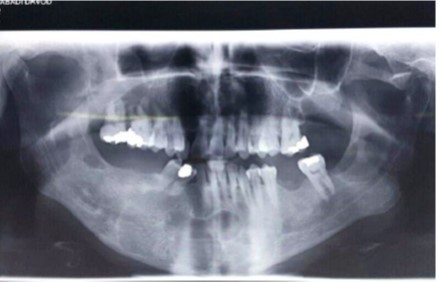

The panoramic radiographs showed seven cysts in the mandible and maxilla. The patient was then referred to the surgical unit of the School of Dentistry. A CT scan was performed in order to better examine the patient and the images obtained revealed multiple extended cysts in the posterior and anterior mandible and maxilla with no swelling. The CT scan and panoramic radiographs showed multiple radiolucencies with well-demarcated borders, cortical margins and different sizes (Figure 3 and Figure 4). The interpretation of the radiographic images diagnosed the patient with radicular cysts and odontogenic keratocysts. The clinical examination of the patient revealed no systemic diseases or symptoms in the skin and the involved areas. The chest and skull radiographs also showed no symptoms.

Figure 3.The panoramic radiograph showing multiple cysts in the maxilla and mandible

The panoramic radiograph showing multiple cysts in the maxilla and mandible

The present case report found no symptoms in the skin of the patient’s hands and legs and in his appearance in the clinical examination, and also no symptoms in his skull and chest radiographs. The radiographs in this case report showed seven well-circumscribed unilocular radiolucencies in the mandible and maxilla.